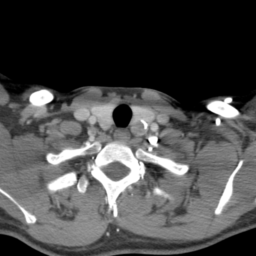

![]() |

| (a) | (b) | (c) | (d) |

Unsupervised Categorization: Our category discovery clusters are generally visually coherent within the cluster and size-balanced across clusters. However, image clusters formed only based on text information (of radiology reports) are highly unbalanced [49], with three clusters inhabiting the majority of images. Note that our method imposes no explicit constraint on the number of instances per cluster. Fig. 6 shows sample images and their top-10 associated key words from two randomly selected clusters (more results are provided in the supplementary material). The LDPO clusters are found to be clinically or semantically related to the corresponding key words, which describe presented anatomies, pathologies (e.g., adenopathy, mass), their associated attributes (e.g., bulky, frontal) and imaging protocols or properties.

The category discovery clusters employing our LDPO method are found to be more visually coherent and cluster-wise balanced in comparison to the results in [49] where clusters are formed only from text information ( radiology reports). Fig. 7 Left shows the image numbers for each cluster from the AlexNet-FC7-Topic setting. The numbers are uniformly distributed with a mean of 778 and standard deviation of 52. Fig. 7 Right illustrates the relation of clustering results derived from image cues or text reports [49]. Note that there is no instance-balance-per-cluster constraints in the LDPO clustering. The clusters in [49] are highly uneven: 3 clusters inhabit the majority of images. Fig. 6 shows sample images and top-10 associated key words from 5 randomly selected clusters (more results in the supplementary material). The LDPO clusters are found to be semantically or clinically related to the corresponding key words, containing the information of (likely appeared) anatomies, pathologies (e.g., adenopathy, mass), their attributes (e.g., bulky, frontal) and imaging protocols or properties.